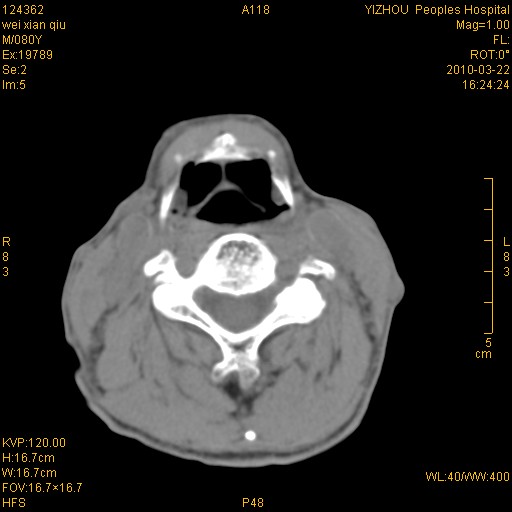

标题: CT25263:喉部占位?

男,80岁.声嘶三月余.

喉前庭右侧壁明显增厚,并见向内突出的软组织密度新生物,表面光滑,其后方软组织层次尚清晰,多考虑:喉部乳头状瘤!建议喉镜并病检!

右侧声们下区新生物,建议行喉镜检查(活检)进一步明确诊断。

支持右侧喉癌,建议喉镜活检。